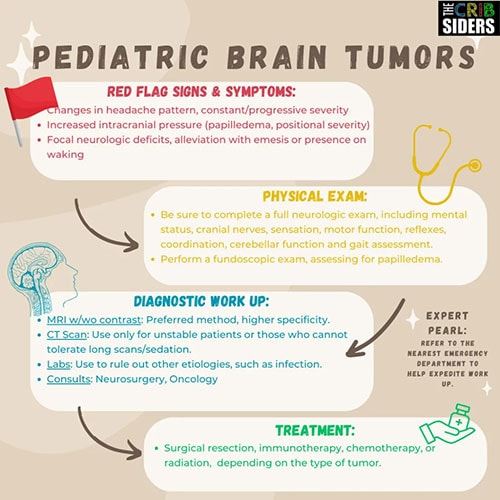

Chiu: As pediatricians, we never really want to miss a diagnosis, but I think a brain tumor in particular is a diagnosis we're all a little afraid of missing. What are some red-flag signs and symptoms we should be looking for?

Hane: The first one that comes to mind, probably for all of us, is headache. We talked a lot about that on the podcast, particularly the specific characteristics of the headache. Worrisome headaches are those that are severe or sudden in onset. They're often persistent and progressive — the pain gets worse. Patients often complain of having pain when first waking up in the morning or positional headaches. Vomiting followed by the headache actually getting better is a big red flag for increased intracranial pressure. Other things we worry about are neurologic symptoms such as dizziness, weakness, visual changes, or frequent falls, particularly a neurologic change in addition to a headache. Those would all be red flags.

Chiu: Let's say we have a patient who comes in with a new-onset headache that improves with vomiting. What should we be doing during that visit?

Hane: Don't panic; fall back on your good clinical skills. Take a good history, asking about any medications they are on — for example, oral contraceptive pills or acne medications, which can cause headache. Take a good social history, asking about smoking and drug use.

Do a full head-to-toe neurologic exam, including cranial nerves, motor function, strength, coordination, gait assessment, and cerebellar function. Perform a fundoscopic exam to look for papilledema in the back of the eye, a sign of increased intracranial pressure.

If you have a high concern for a brain tumor, you should have a really low threshold for getting head imaging. Dr Hummel talked about sending patients straight to the emergency room to expedite the workup. The type of head imaging depends on the patient, the setting where you are, access to resources, and so forth, but he said that if you are putting a child under sedation to get imaging, you really should be getting an MRI with and without contrast. That's the gold standard.

Chiu: What types of treatments are we thinking about at this time?

Hane: Depending on the type of tumor, there's a huge range of treatment options. Your first step is going to be consulting neurosurgery and oncology to figure out a treatment plan. From there, for most pediatric brain tumors, total surgical resection is the gold standard. In addition to that, there may be chemotherapy, immunotherapy, and potentially radiation.